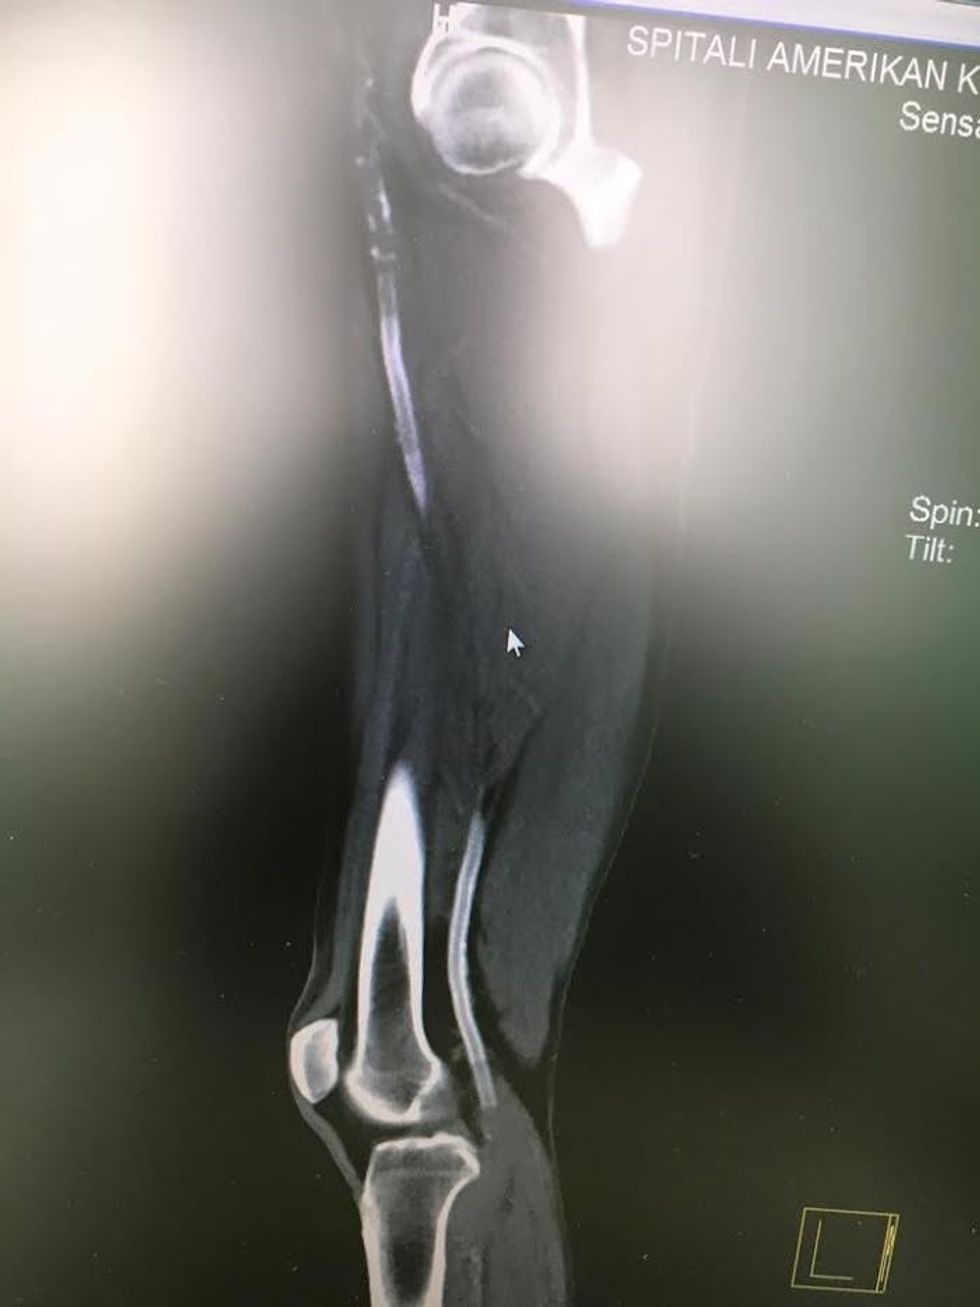

Pacientit i është bërë hapja e stentit periferik të thrombozuar (mbyllur) në gjithë aksin e arterieve të ekstremitetit (këmbës), pa i dëmtuar stentet, procedurë e cila është realizuar me sukses në Spitalin Amerikan nga Dr. Elmi Olluri – Kirurg Vaskular, me ndihmën e ekipit asistues në sallë.

Këto stente pacientit i janë vendosur në SHBA para disa viteve. Një procedurë e tillë e realizuar në kohë urgjente dhe me profesionalizëm, rezultoi me shpëtimin e këmbës nga amputimi, amputim i cili në qendrat e rajonit do të ndodhte thuajse 100 për qind. Por, falë profesionalizmit dhe përvojës arrihet që edhe stentet të hapen me sukses.